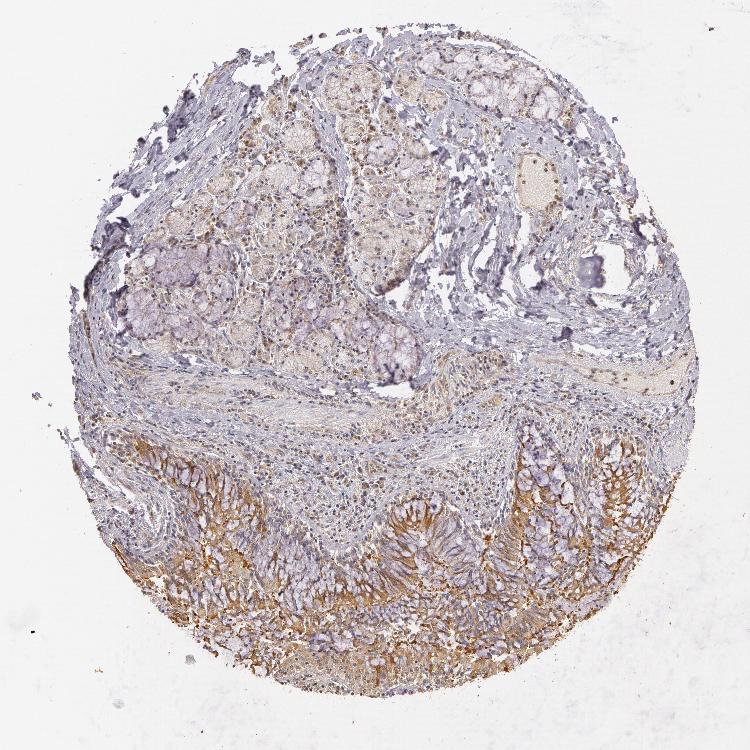

ADIPOSE TISSUE - Antibody stainingi

Antibody staining in the annotated cell types in the current human tissue is reported as not detected, low, medium, or high, based on conventional immunohistochemistry profiling in selected tissues. This score is based on the combination of the staining intensity and fraction of stained cells.

Each image is clickable and will lead to virtual microscopy that enables deeper exploration of all samples and also displays staining intensity scores, fraction scores and subcellular localization as well as patient and tissue information for each sample.

Antibody HPA000903Antibody CAB006244

Adipocytes MediumMedium